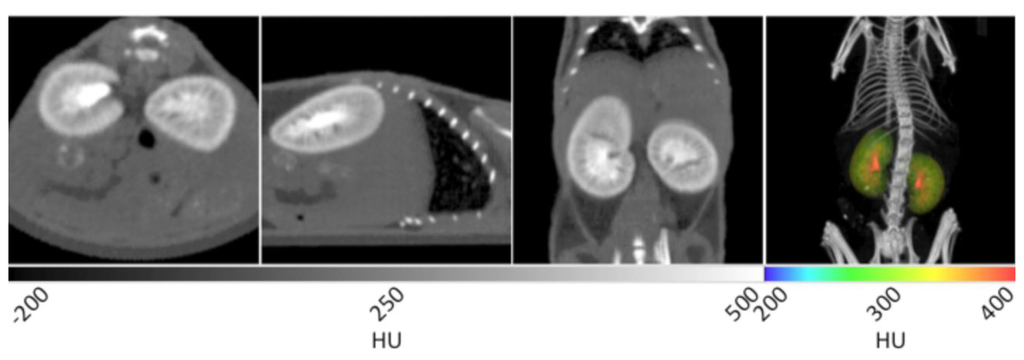

With the aid of Visipaque™ 320, renal structures are greatly enhanced during CT imaging. In Figure 6, the renal pelvis (inner core structure) is immediately distinguishable from the renal cortex (outer rim) and medulla (intermediate space in between). In the sagittal plane, the cortex can be differentiated from the medulla by its higher degree of contrast enhancement. In addition, major and minor calyxes can be identified. Although not in the same plane as the kidneys, the bladder is also readily identified using Visipaque™ enhancement. For manual segmentation, the kidneys were separated into an independent data set by drawing a VOI around them and masking the surrounding tissue. This data set was then false colored using a rainbow scale, and overlaid onto the CT to yield the 3D visualization given in the right frame of Figure 6. The gross anatomical structure and positioning of the kidneys can be observed after the original CT image is overlaid to provide spatial reference points. The highly contrast-enhanced, red regions correspond to the renal pelvises, while the medulla and cortex are noted in yellow and green. Due to the high iodine content of Visipaque™ 320, such studies can be conducted with doses as low as 30 µL without sacrificing the diagnostic abilities of the reagent.